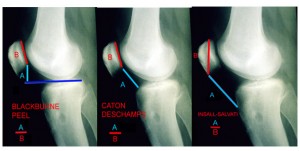

- Joelho